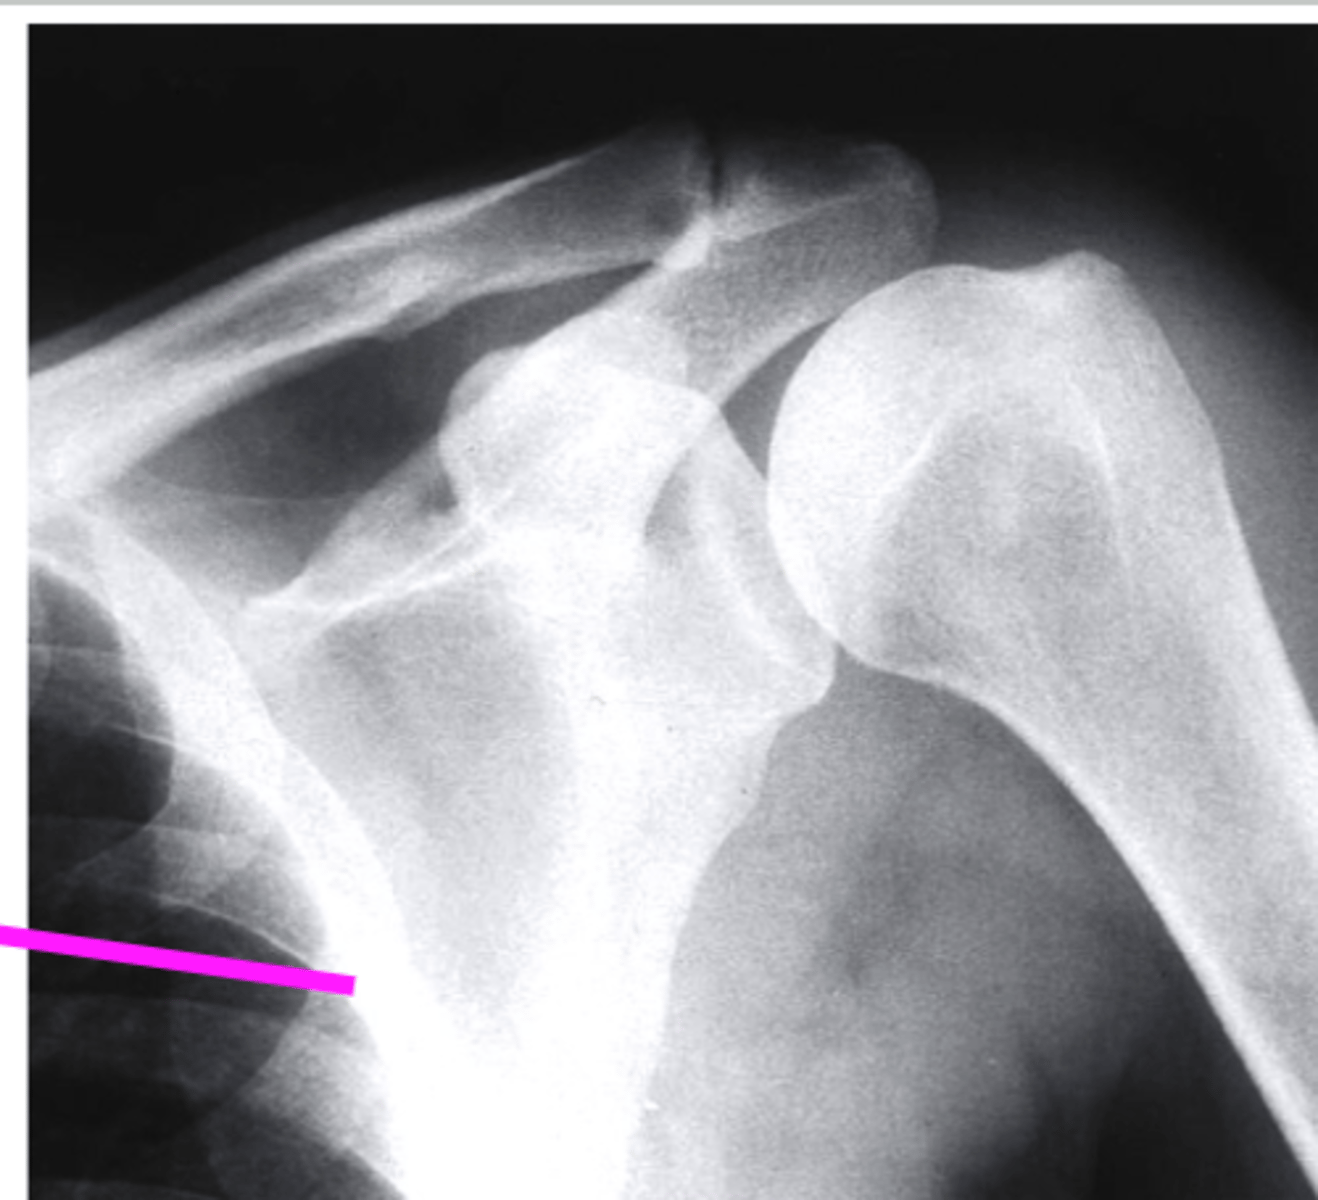

shoulder axillary

what view is this?

clavicle

what does the pink line point to?

the coracoid process

the glenoid fossa

acromion

humeral head